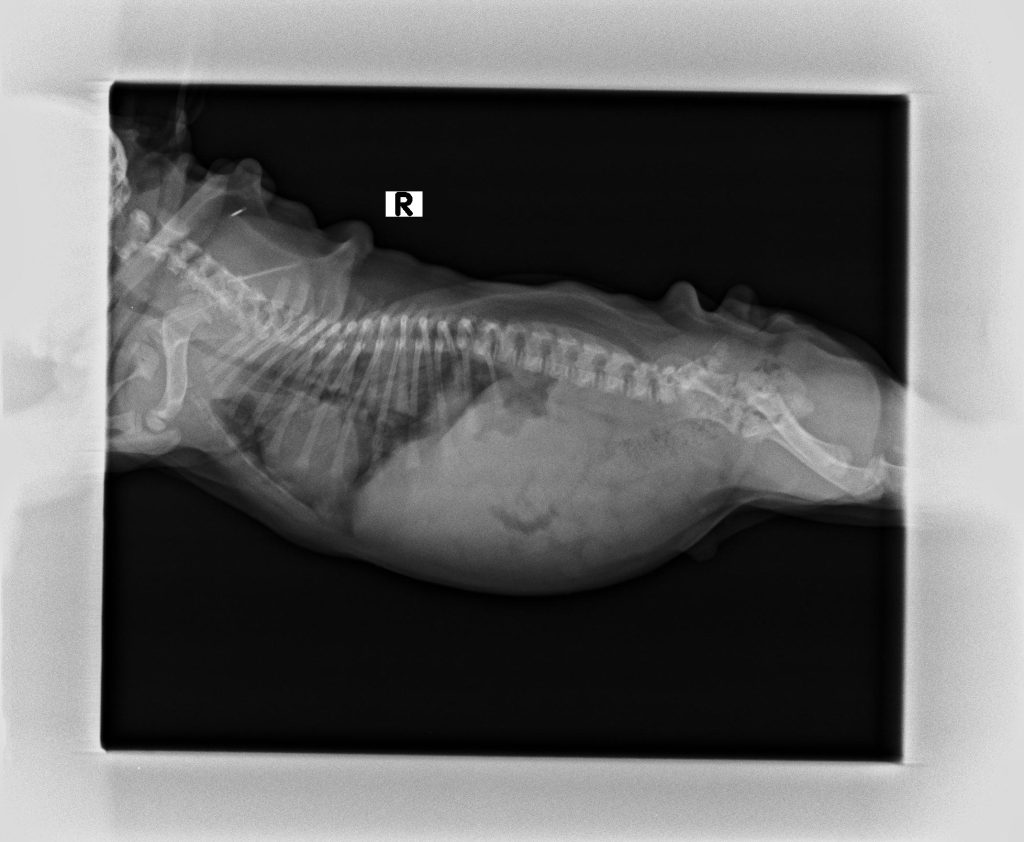

- X光檢查:檢視肺部、氣管、心臟大小